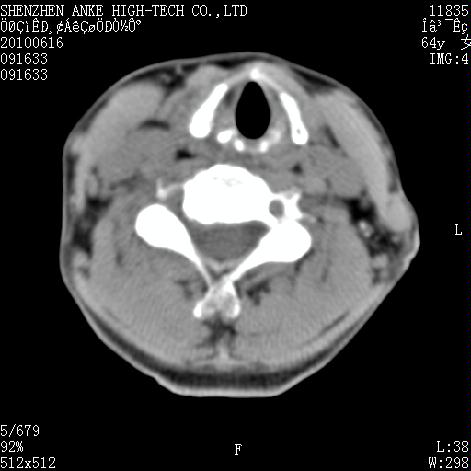

标题: CT27132:患者女,64岁,颈部及全身多处包块,现觉吞咽困难4 [打印本页]

标题: CT27132:患者女,64岁,颈部及全身多处包块,现觉吞咽困难4

右侧甲状腺占位,肿瘤可能性大,癌

右侧甲状腺癌伴右颌下腺淋巴结转移

右侧甲状腺癌伴淋巴结转移

右侧甲状腺癌伴淋巴结转移可能性大

右侧甲状腺癌伴淋巴结转移可能性大。

右侧甲状腺癌伴右颌下腺淋巴结转移!建议增强!